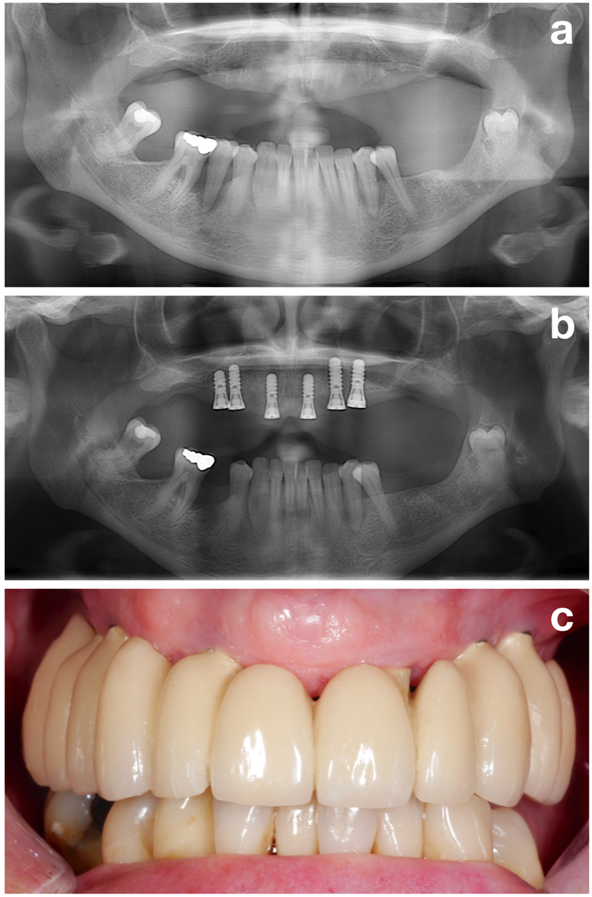

The NIWOP concept (Figure 1) is split into 3 major aspects: (1) Pre-treatment phase, (2) implant installation, and (3) recall or supportive treatment.

The first part (i.e., the pre-treatment phase) aims to perfectly prepare the patient for the actual implant installation by evaluating all potential risk factors but focusing on one of the most important ones: establishment of a stable periodontal situation (Figure 2).